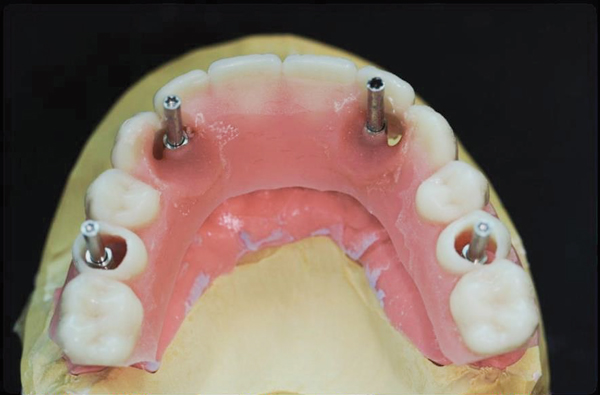

Fig 7. Sclar Center Protocol Provisional Prosthesis Guide used in surgical and restorative procedures. Treatment windows provide for restoration-driven implant placement and simplified restorative procedures.

Figure 7

Fig 9. Restoration-driven implant placement—Optimal implant position and distribution is achieved as a result of using the provisional prosthesis guide.

Figure 9